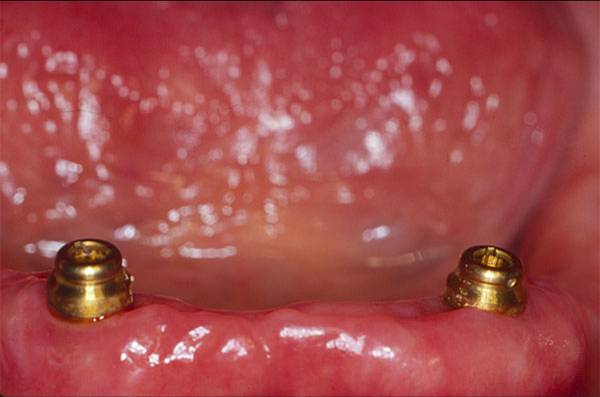

Locator® Attachments

For economy, ease of delivery, and predictable sucess; you can't beat the Locator® Attachments for implants. The Locator® Attachments are now available for most of the major implant platforms making this a viable consideration for many treatment plans involving multiple implants. Few things in restorative dentistry have proven to be as simple, esthetic, and cost effective while providing such high patient and doctor satisfaction.